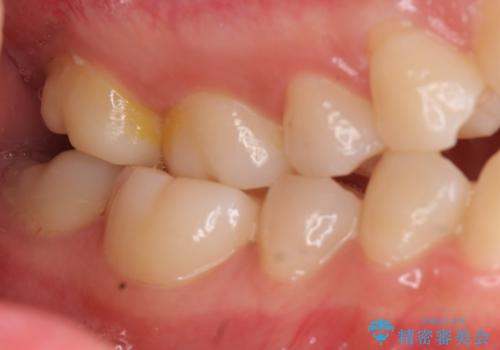

前歯は重度のがたつき、また奥歯はすれ違っていました。

上下の顎の幅もあっておらず、成人でしたが手術なしで上あごを骨から広げる処置(急速拡大装置)を行いました。